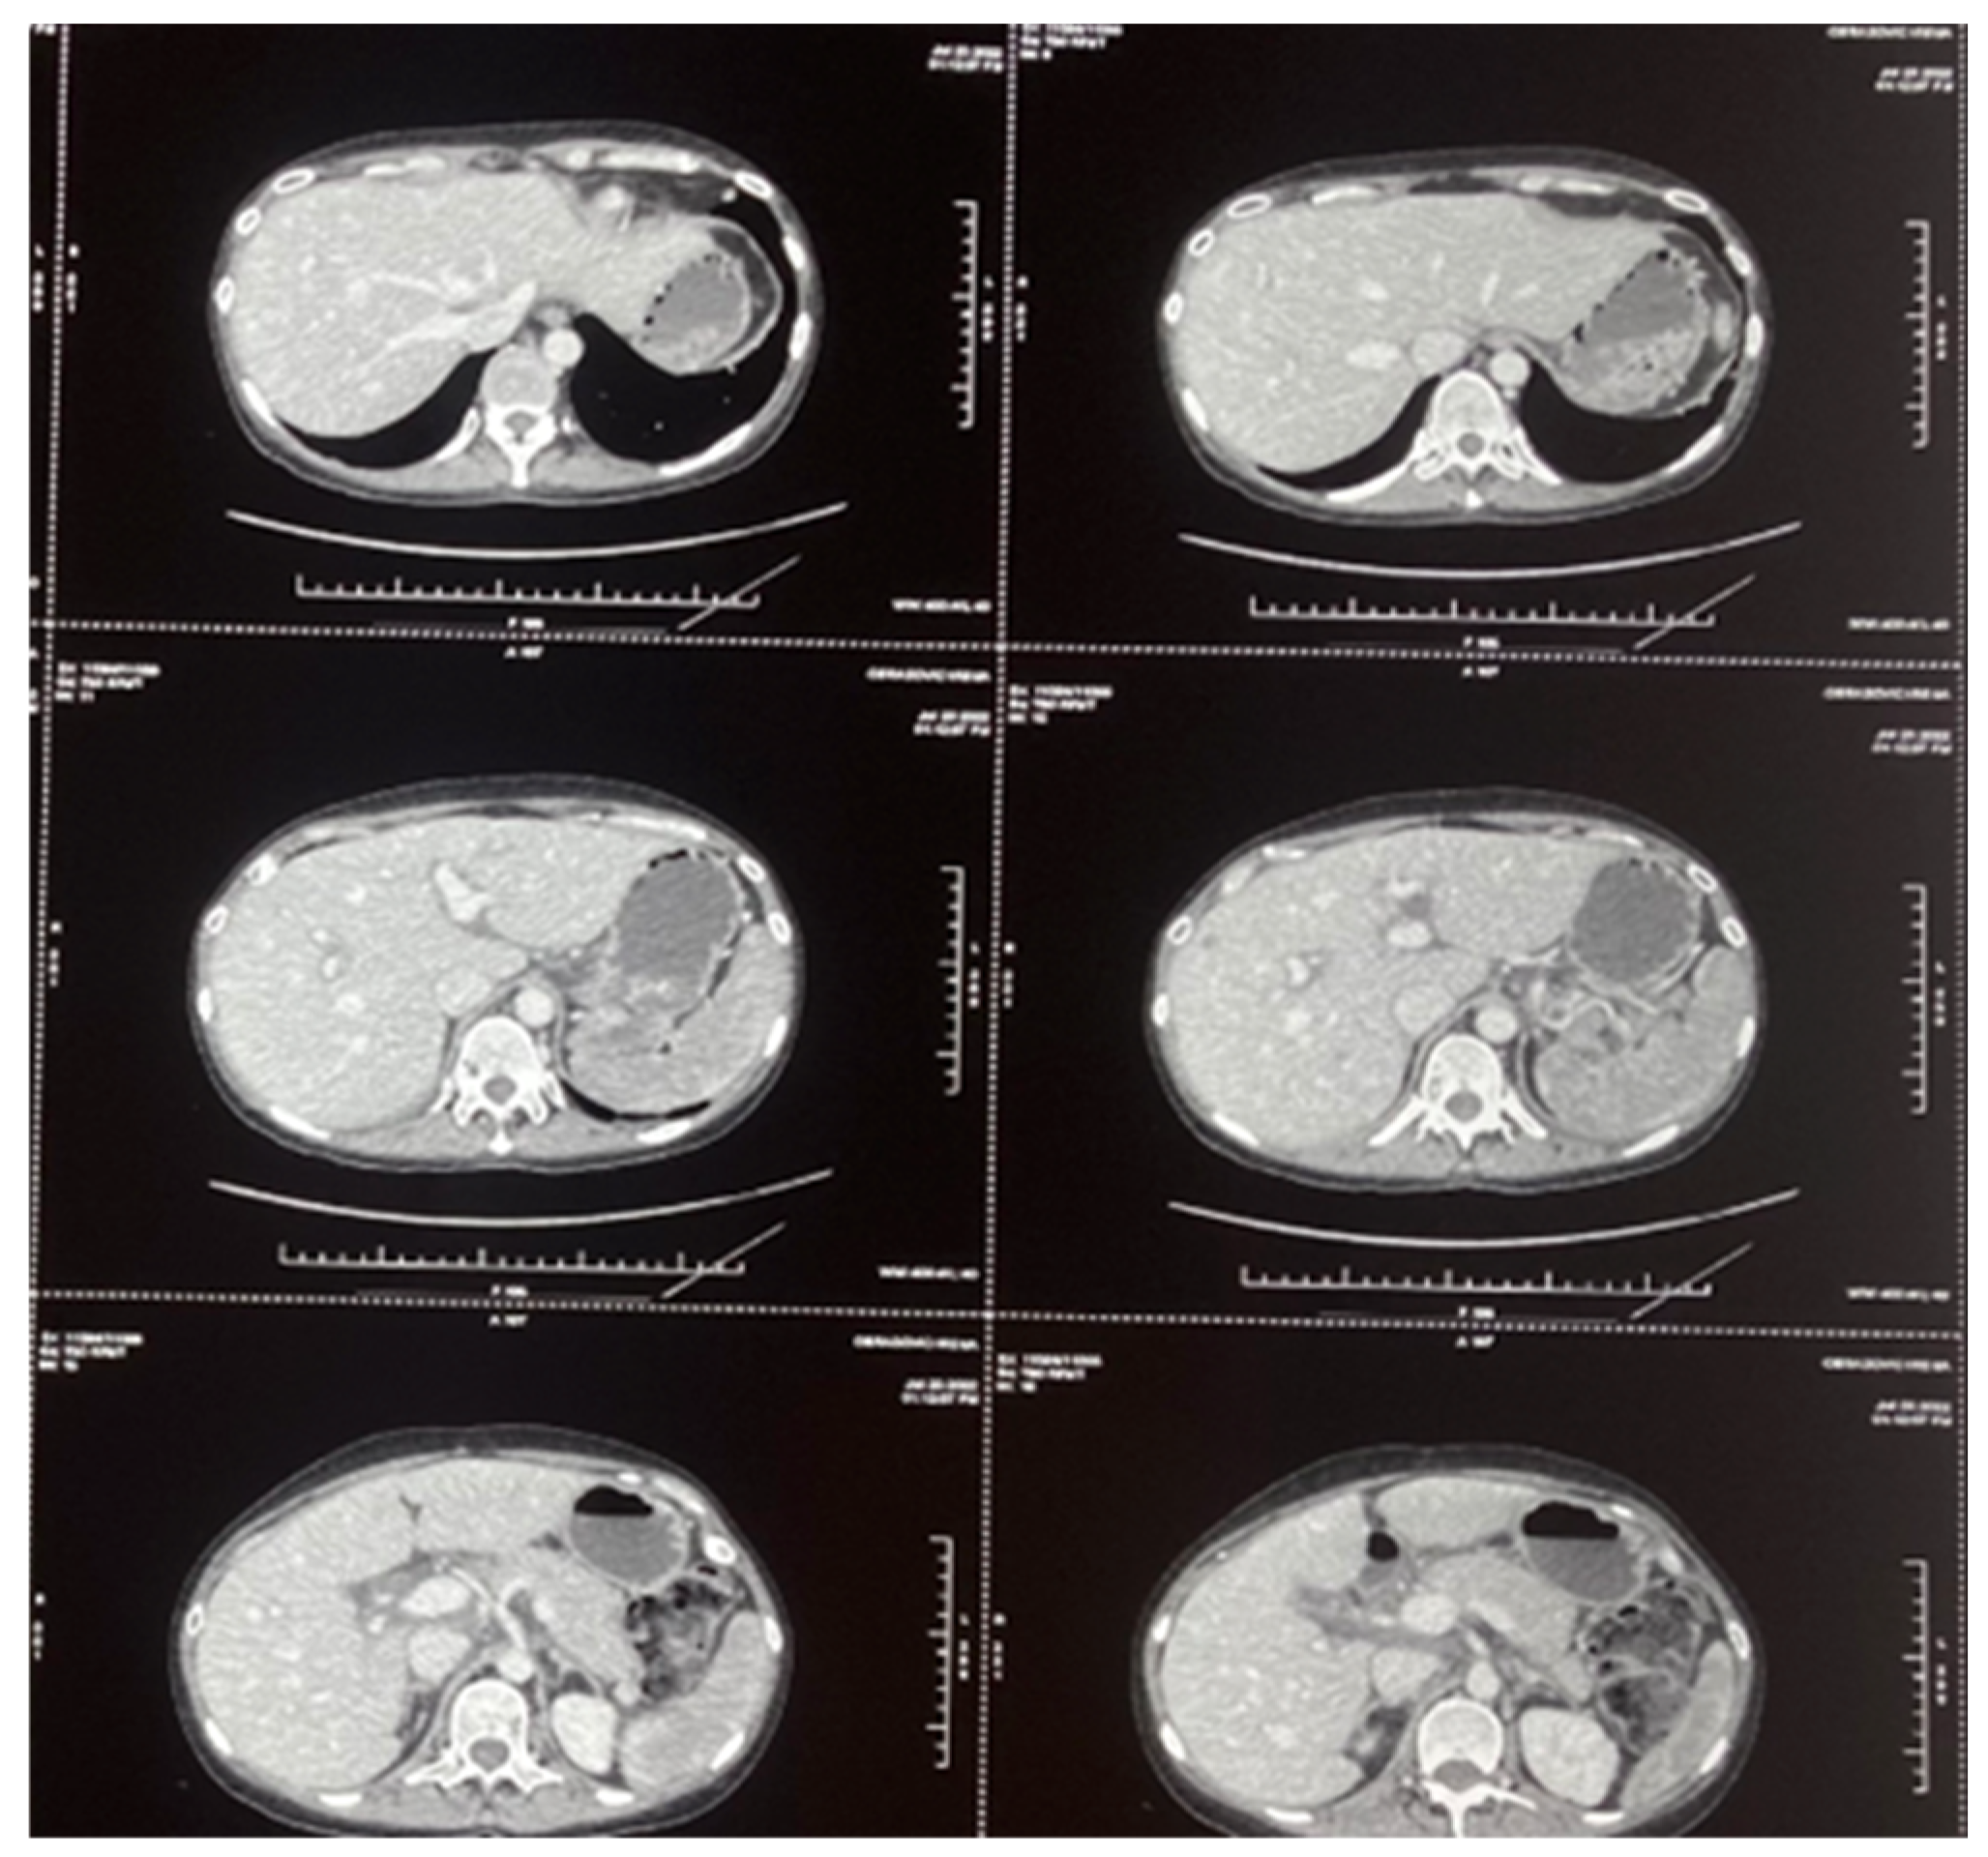

2.1. Case 1

2.2. Case 2

2.3. Case 3